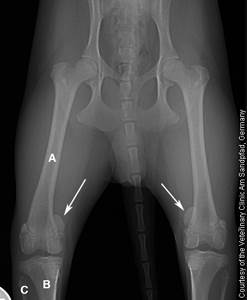

Диагностика вывиха коленной чашечки проводится на основании клинической картины и рентгенографии в двух проекциях (прямая и латеральная). Требуется исключить другие патологии со схожими симптомами – в первую очередь, болезнь Пертеса. Также в некоторых случаях медиальный вывих может сопровождаться разрывом передней крестовидной связки, необходимо четко разграничить эти две патологии.